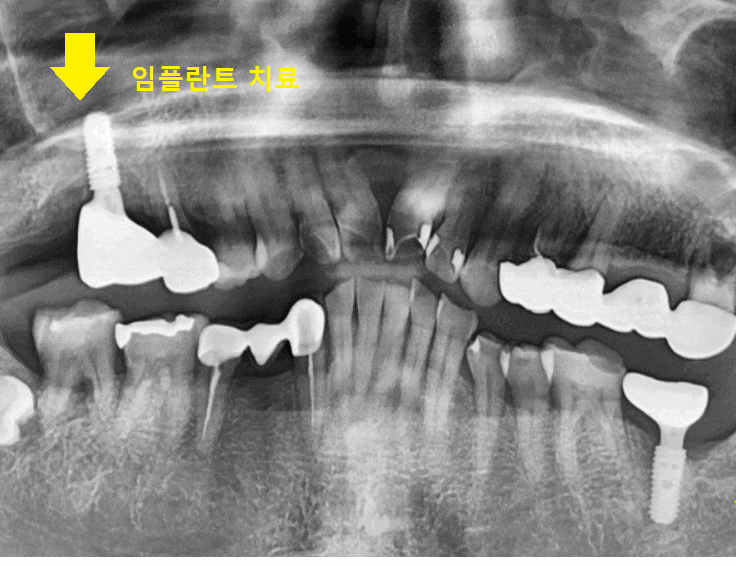

명일역 근처 치과 환자분이 처음 내원하셨을 때 사진입니다.

오른쪽으로 식사를 거의 못한다고 하셨습니다.

23.10.05

오른쪽 위아래 어금니 모두 문제가 있었습니다.

첫번째로 잇몸뼈가 많이 녹았고요~

치아를 건들여보았을 때

흔들흔들 하더라고요.

두번째로 오른쪽 위 어금니

육안으로 잇몸 뾰루지처럼 볼록하게

올라온게 보이시죠??

치아 뿌리 염증이 잇몸 밖으로

올라온겁니다.